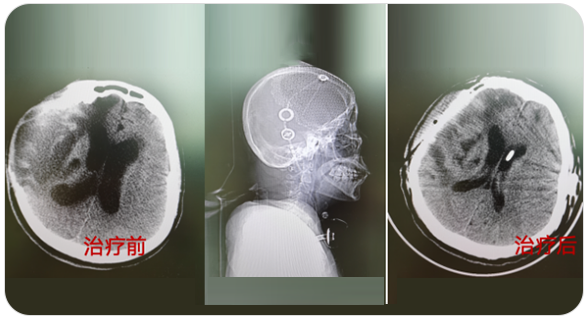

精通顱內(nèi)動脈瘤介入栓塞和手術(shù)夾閉雙技術(shù),系統(tǒng)掌握腦動靜脈畸形、頸內(nèi)動脈海綿竇漏、硬腦膜動靜脈漏等顱內(nèi)血管疾病的診療和手術(shù),精通頸動脈、椎動脈狹窄的血管內(nèi)重建技術(shù),以及頸動脈狹窄的內(nèi)膜剝脫手術(shù)技術(shù)。在顱內(nèi)腫瘤、椎管內(nèi)腫瘤、顱腦損傷、高血壓腦出血等疾病的診治和手術(shù),腦功能性疾病立體定向手術(shù)治療等方面也積累了豐富的經(jīng)驗。

擅長腦血管病(出血與缺血)的神經(jīng)介入與微創(chuàng)手術(shù),能熟練開展腦外傷、重度顱腦損傷的救治工作。